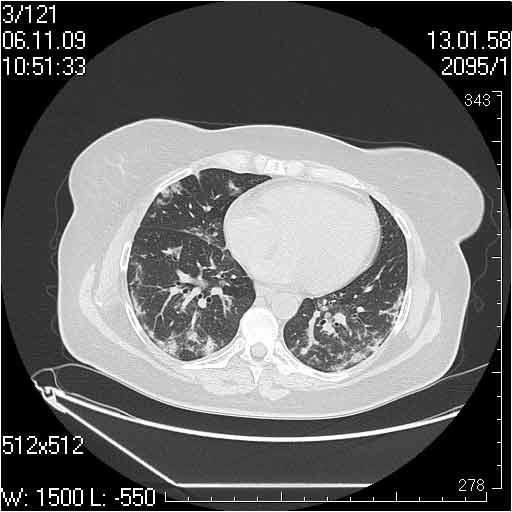

Случай №2

Мужчина 54 лет

Случай 2: картина патологических изменения довольно типична: GGOs & thickened interlobular septas = "crazy paving" sign. Наличие плотностей по типу матового стекла в сочетании с утолщением междолевых перегородок, даёт признак булыжной мостовой; на первом месте будет стоят диагноз альвеолярных протеиноз.